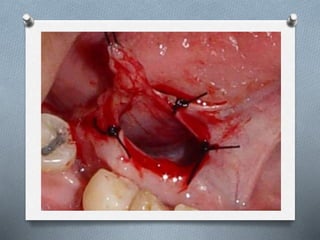

La ránula es una lesión mucocele que se forma unilateralmente en el piso de la boca, asociada al conducto de Wharton o de Bartolino. Puede ser causada por traumatismos u obstrucciones. Se presenta como una masa traslúcida, de color normal o morado-rojizo, mayor a un mucocele común. Su diagnóstico se realiza clínicamente y puede confirmarse con tomografía computarizada o resonancia magnética. Los tratamientos incluyen marsupialización, escisión de la glándula